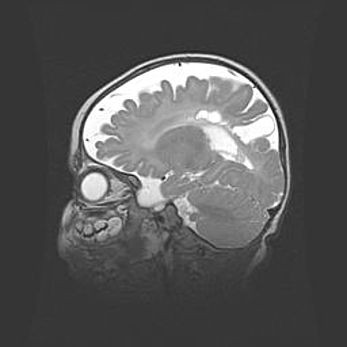

Аномалия Денди-Уокера. Признаки гипоплазии мозолистого тела.

Возраст: 5 месяцев 3 дня

Вес: 5550 г

Пол: мужской

Окружность головы: 39 см

Срок гестации: 40 недель

Аномалия Денди-Уокера – это порок развития головного мозга, для которого характерна триада симптомов: гипотрофия или аплазия червя мозжечка и/или полушарий мозжечка, расширение четвёртого желудочка с формированием ликворной кисты задней черепной ямки, гипертензионная гидроцефалия различной степени.

Гипоплазия мозолистого тела относится к дефектам внутриутробного этапа развития мозговой ткани, возникающим в процессе закладки структур головного мозга, что происходит на начальных этапах развития эмбриона.